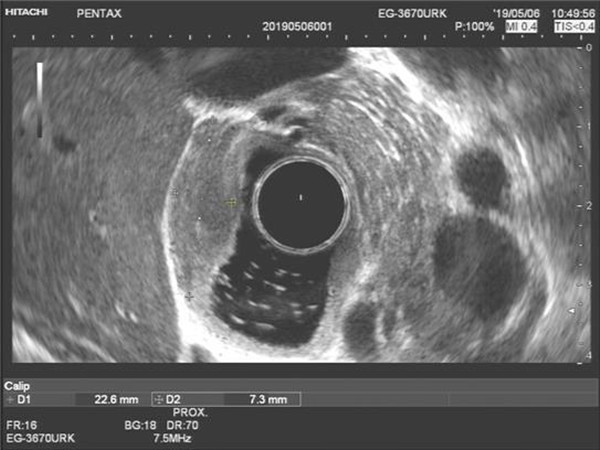

患者为男性18岁青年。间断性胃痛数年,近1年症状渐明显加重。2018年8月超声胃镜发现十二指肠占位,横截面约1.1cm,2019年2月复查内镜,肿物直径约1.5cm。近日门诊复查,肿物直径增大至2.2cm,门诊以“十二指肠肿瘤”收治入院。由于肿物逐渐增大,性质不明确,患者心理负担较重,强烈要求手术切除。但病变位于十二指肠球降移行部小弯侧,向腔内椭圆状突出,单纯外科手术,容易迷失病变,手术路径不畅。单纯消化内镜切除,要全层切开,切口内镜缝合困难较大。经普外科和消化科会诊讨论后,认为双镜联合手术较为稳妥可行。在普外科主任陈熹教授和消化科主任王进海教授的协调指导下,于2019年05月21日实施腹腔镜-胃镜联合手术。在静吸复合全麻下,消化内镜组由邹百仓副主任医师主刀,安苗护师协助配合。腹腔镜组由吴涛副主任医师主刀,杨屹副主任医师及范萌主治医师协助。胃镜下确定肿瘤部位后,粘膜下注射后环切瘤体周围粘膜,暴露瘤体,剥离至肌层,瘤体基底部与浆膜黏连,随行全层切开,完整切除瘤体,创面直径3cm,创面无活动出血,切除时间约30分钟。腹腔镜组随行创面缝合关闭,腹腔镜下探查切口部位及大小后,逐层严密缝合,冲洗腹腔,肝下间隙留置乳胶引流管,查腹腔内无活动性出血,清点器械辅料无误后,缝合关闭刺口,逐层关腹术毕。瘤体标本大小2.0X2.0X1.5cm。术后患者安返病房,手术全程约70分钟。术后患者恢复稳定,3天后进食,6天后出院。

超声内镜病变图